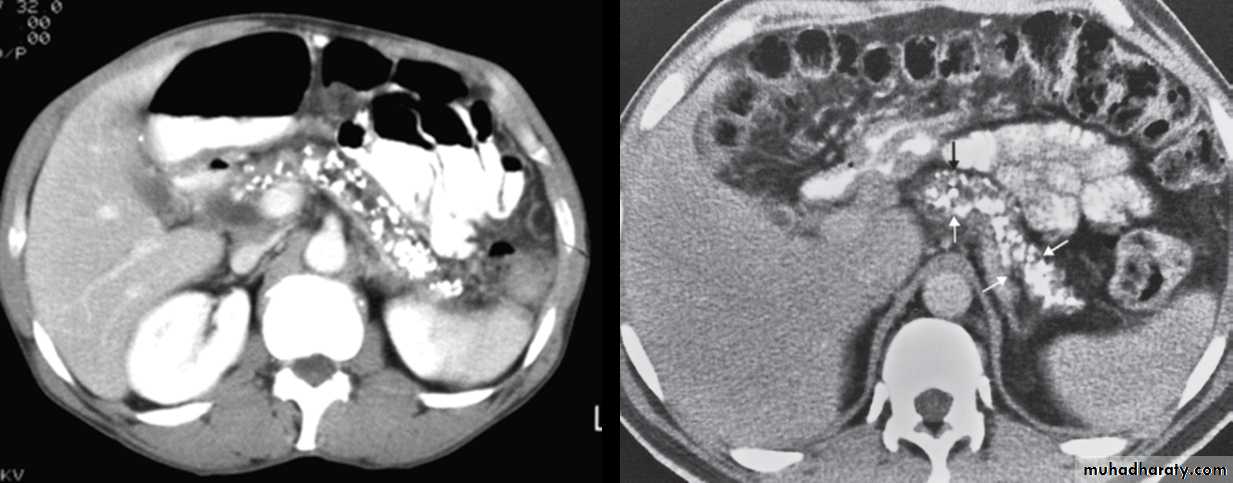

CT findings of acute appendicitis:

• CT shows a swollen appendix.

• Soft tissue stranding pattern in adjacent Fat. This stranding pattern is a highly useful sign on

• CT indicating edema in fat adjacent to inflammation.

• Large fecoliths at the base of the appendix.

• Complication: abscess, inflammatory mass.

CT signs of acute diverticulitis include

• Localized bowel wall thickening• Soft tissue stranding or haziness in pericolonic fat.

• Gas in the bladder may indicate formation of a colovesical fistula.

• Abscess.